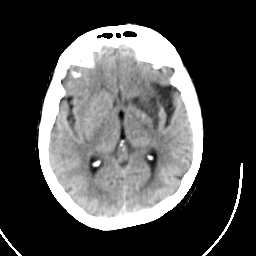

CT Study #1 -- Slice #13